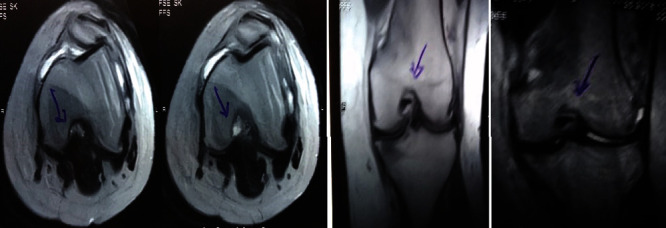

治療后一個(gè)月進(jìn)行隨訪(fǎng)。在第一次細(xì)胞治療后,患者的疼痛明顯減輕。第二次療程后,她沒(méi)有疼痛,并注意到運(yùn)動(dòng)范圍有所改善。持續(xù)的物理治療也觀(guān)察到下肢肌肉力量的增加。從治療開(kāi)始(11個(gè)月前)到最后一次隨訪(fǎng)(4個(gè)月前),患者按照建議的飲食和基于運(yùn)動(dòng)的方案減重了11公斤。因此,她現(xiàn)在整體身體健康,能夠更舒適地進(jìn)行日常生活活動(dòng)。表3顯示治療前后的MRI檢查結(jié)果。人物的圖1和的和圖2顯示半月板撕裂的治療前和治療后(1年后)圖片。觀(guān)察到損傷程度的改善圖2。